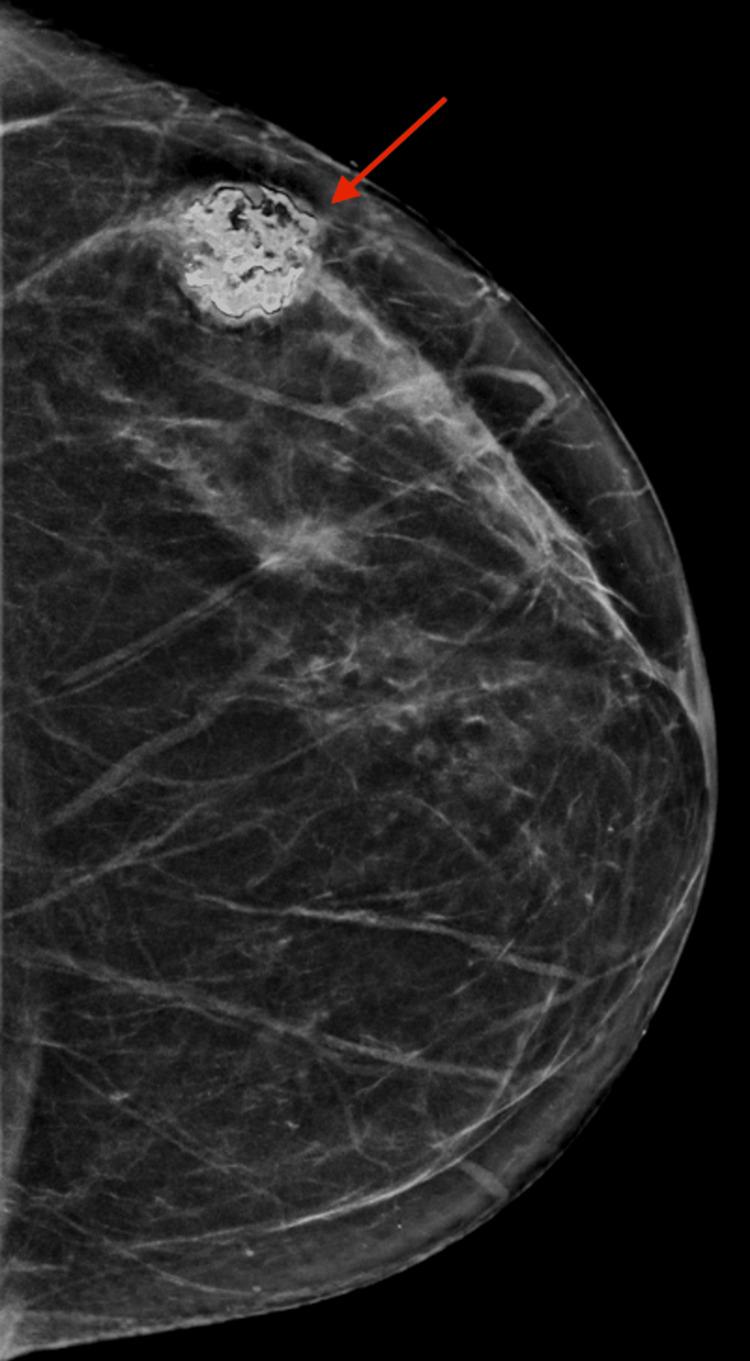

伴有软骨母细胞性骨肉瘤分化的恶性叶状肿瘤:一例报告

Malignant Phyllodes Tumor With Chondroblastic Osteosarcomatous Differentiation: A Case Report.

Malignant phyllodes tumors (MPTs) represent the most pernicious type of intralobular stromal proliferation known as a "fibroepithelial lesion" (FEL). They comprise a small fraction of breast malignancies and can present as either a pure MPT or sometimes include a heterologous component (liposarcoma, chondrosarcoma, osteosarcoma, or rhabdomyosarcoma). Of the fraction of MPTs that include heterologous components, very little about those with chondroblastic osteosarcomatous differentiation has been described in the literature. As such, a characteristic staining profile has yet to be established, even though morphological analysis is the cornerstone of diagnosis. The few reported cases have described a poor prognosis. Therefore, we present a case of MPT with chondroblastic osteosarcomatous differentiation to contribute to the dearth of literature examining this entity.

摘要